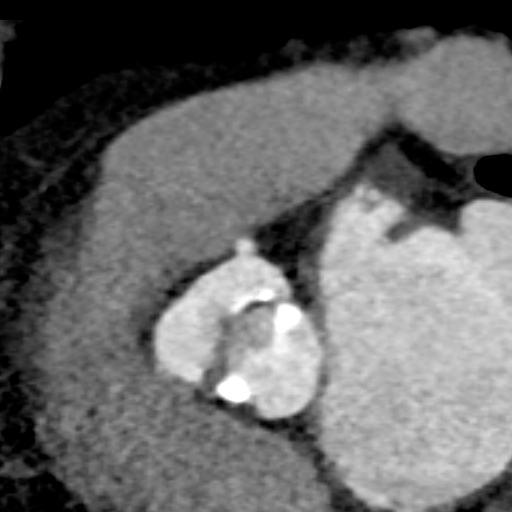

主动脉CT

主动脉瓣环平均直径:22.4mm

左室流出道平均直径:23.2

左冠脉开口:10mm

右冠脉开口高度:14.7mm

患者为功能性二叶瓣,左右瓣叶融合,左冠脉开口低,窦部大,冠脉风险低。

袁义强院长总结了该病例特点:功能性二叶瓣主动脉瓣狭窄,患者有心衰症状,解剖适合TAVR,年龄66岁,存在明确TAVR手术适应症。选择右股动脉入路,根据CT测量分析选择瓣膜大小,窦部情况可,瓣环平均直径22.4mm,选择植入24mm瓣膜。

监护麻醉,经右侧股动脉全麻行TAVR,选用22mm球囊扩张,查看冠脉风险VitaFlow24瓣膜植入。

球囊预扩

瓣膜初始定位

即刻超声评估示瓣周漏显著降低